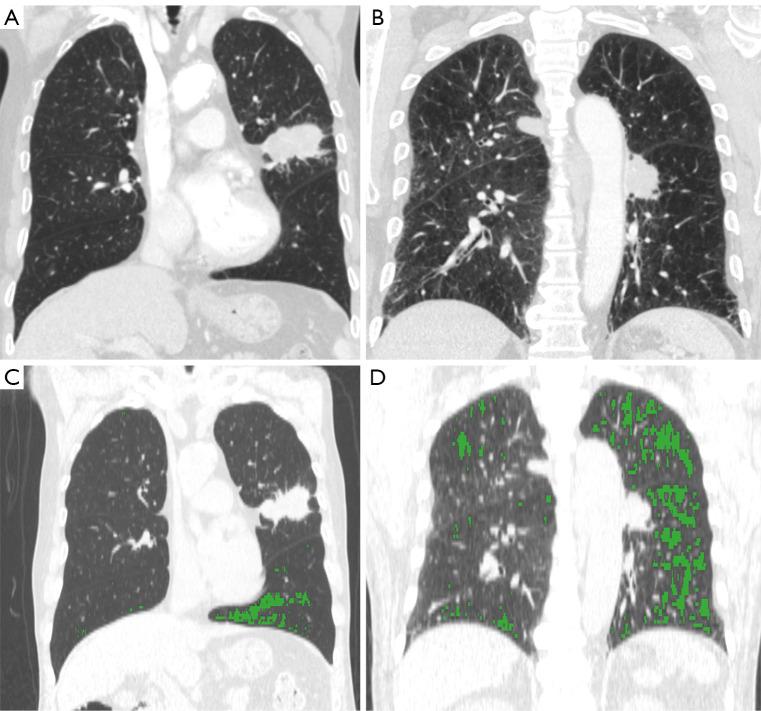

Herein, 177 patients with COPD and lung cancer were prospectively recruited. Plasma ctDNA was genotyped using targeted deep sequencing. Comprehensive clinical variables were collected, including the emphysema index (EI), using chest computed tomography. Machine learning models were constructed to predict ctDNA detection.

前瞻性招募了177例COPD合并肺癌患者。使用靶向深度测序对血浆ctDNA进行基因分型。收集综合临床变量,包括使用胸部计算机断层扫描的肺气肿指数(EI)。构建机器学习模型以预测ctDNA检测。